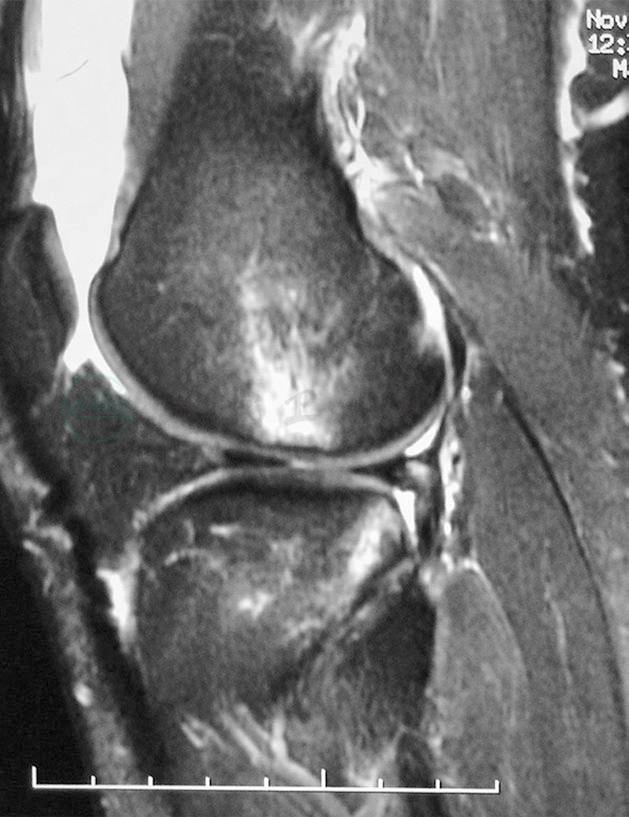

(2)磁共振成像

磁共振成像以其优质的图像、对人体的无创性而受到越来越多的重视。磁共振成像应在冠状面和矢状面两个平面上扫描影像,扫描厚度每层3~5mm以获得交叉韧带的低密度影像(图8)。如果影像连续性中断,则可以判断韧带损伤。磁共振成像对于前交叉韧带损伤有很高的诊断价值,它的敏感性92%~100%,特异性89%~97%。

图8磁共振成像正常前交叉韧带影像

引自:实用骨科学(第2版).第2版.ISBN:978-7-117-22817-6.主编: